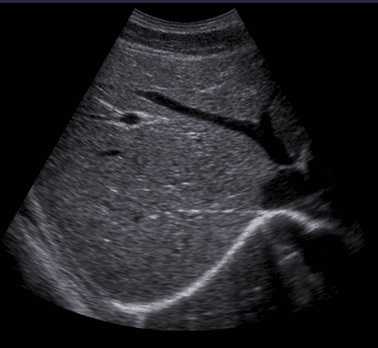

B型(Brightness modulation)

• 显示亮度调制的信号

• 在超声诊断仪的显示器上,以亮度调制的方式,显示声束扫描平面内人体组织的断面图象。

• B型显示给出的是人体的解剖结构图象。

B超是B型超声的简称,即我们通常所说的“黑白超”。它是以不同辉度的光点强弱显示脏器及病变的二维切面图像的超声检查方法。

( 简述: 以亮度的强弱显示组织回波信号的强弱,并转为二维灰度图像。二维断面图像,实时显示组织结构,形象直观。)

B型超声诊断

B型超声诊断基于超声波在人体内到达不同组织界面,反射的回波信号就不同(组织距离探头越远,反射回波信号越弱)这一原理,以不同明暗程度的光点(即灰阶形式)表示不同强弱程度的回波信号,即反应不同的组织界面。

把不同明暗程度的光点连续起来就构成了被探测部位的二维断层图像或切面图像,即声像图。